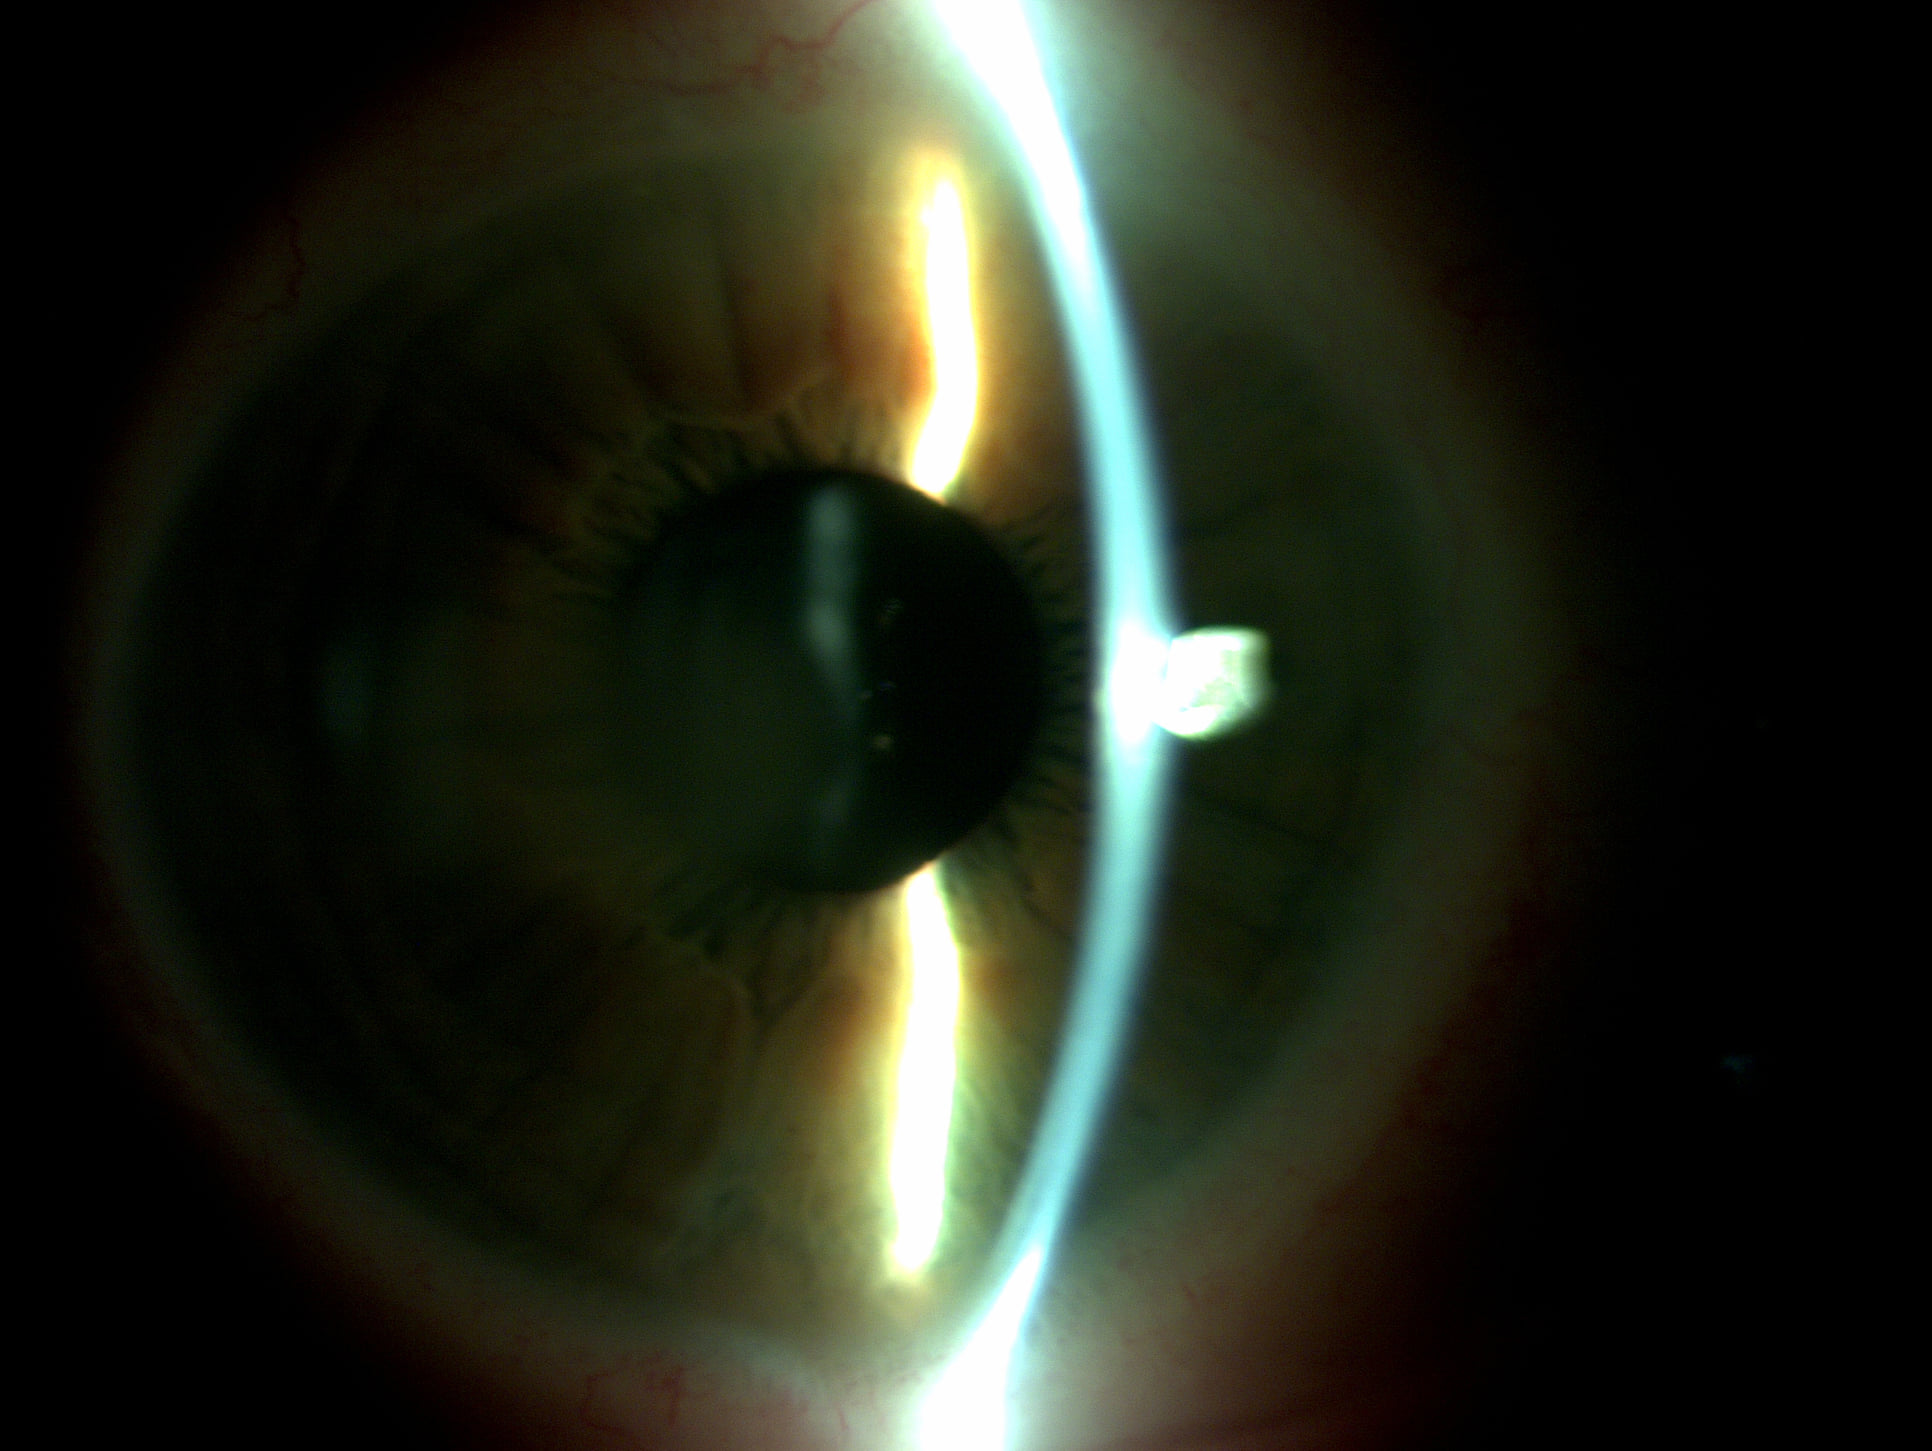

Mai jos, fotografii ale mai multor pacienti de-ai nostri cu Corneea Guttatta în faze medii, sau chiar avansate, la care am efectuat doar operația de cataractă, în urma căreia corneea a „supraviețuit” cu brio și nu a mai fost nevoie – cel puțin până acum – de un trasplant de cornee.